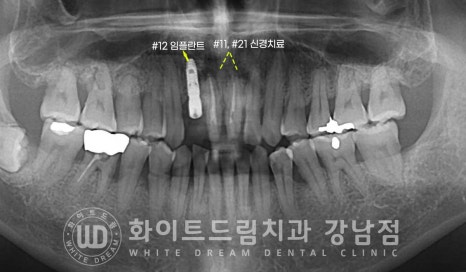

환자분이 증상을 호소하시는 치아는

앞니 3개 (12, 11, 21번 치아)입니다.

육안으로 보기엔 11번, 21번 치아 사이 큰 충치가 발생해있고

11번 치아가 전체적으로 어둡게 변색된 것이 확인됩니다.

그리고 동요도 검사 시 12번 치아가 심하게 흔들림을 호소하고 있었는데

치아의 상태를 보다 정확하게 확인하기 위해 치근단 사진을 촬영해 봤습니다.

12번 치아의 치주 인대가 손상되어 염증이 발생했고

이로 인해 주위 잇몸뼈가 녹기 시작한 것으로 추측되었습니다.

또한 11번 변색된 치아 끝 부위에 치아 뿌리 염증이 자리를 잡고 있는 것이 확인됩니다.

아마 외상을 당하셨을 때 치수가 손상되었고 천천히 괴사가 일어나

치아 뿌리에 염증이 발생한 것으로 추측되었습니다.

이 치아 뿌리 염증과 인접면 충치 치료를 진행하기 위해

11번, 21번 치아는 신경치료를 진행하기로 하였고

잇몸뼈가 심하게 녹아 흔들림이 심한 12번 치아는 발치 후 임플란트를 식립하기로

환자분과 상의 후 결정되었습니다.